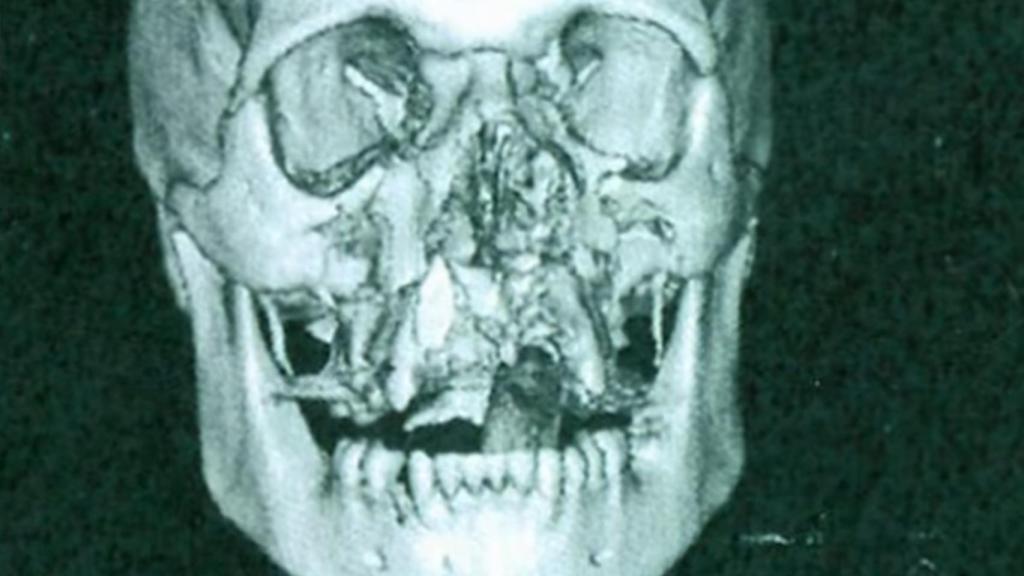

A Jack le tuvieron que contar qué había sucedido casi dos semanas después. "Tenía un derrame cerebral. Me rompí cada hueso de mi cara. Me rompí mi muñeca derecha. Mi pelvis quedó hecha trizas. Me disloqué la pierna izquierda. Y se me rompió la rótula", ha apuntado a la cadena británica. Los doctores advirtieron a sus amigos y familiares del estado del joven; no sabían si iba a superar esa noche. "Honestamente, pensé que había muerto", explicó su hermano.

Una radiografía de la cara de Jack tras el incidente.

Pero contra todo pronóstico, y dos semanas después del accidente, Jack salió del coma.  Sin embargo, la pesadilla seguía allí. "De la forma en que me disloqué la pierna izquierda era muy peligroso, porque estaba cerca de la médula espinal. Me podría haber quedado paralítico", expone. En ese momento comenzó un calvario de operaciones; le colocaron una placa en la pierna, le reconstruyeron la cara, especialmente los dientes. Se había roto cada uno de los huesos de su rostro.